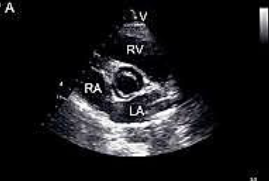

A figura a seguir é tipicamente encontrada em qual dos seguintes pós-operatórios?